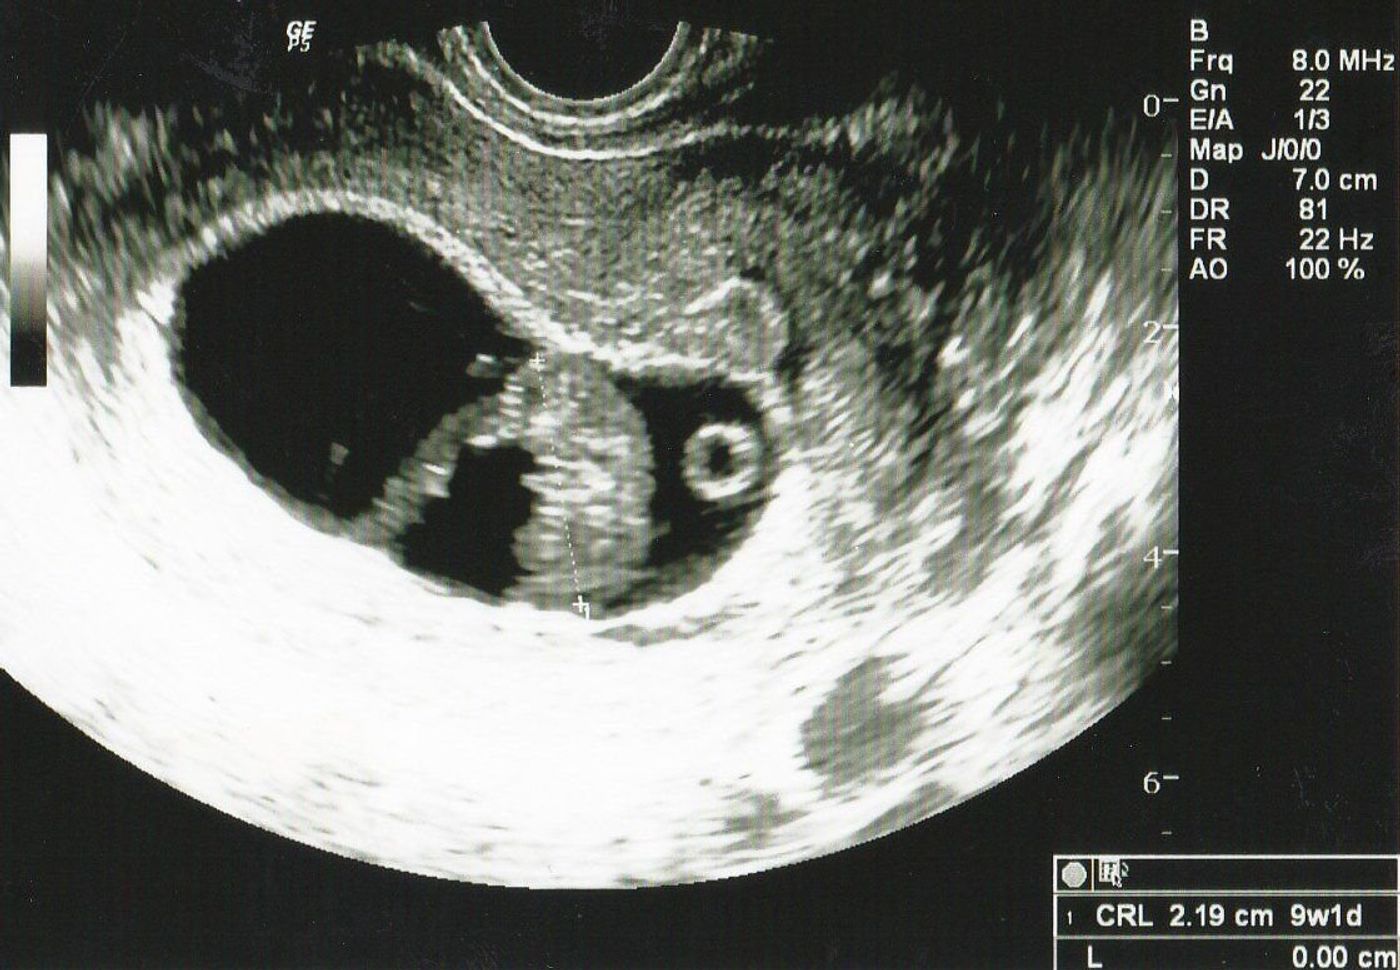

可愛い? 怖い? 妄想力が試されるエコー写真_トーキョー爆誕子育生活 検診に行くと必ず超音波検診で胎児の様子を確認しますが、その際にもらえるのがエコー写真。 白黒で胎内の様子を撮したもので、お子さんをお持ちのパパママであればお馴染みだ League of Legends のチャンピオンEkko(エコー)の全スキンまとめ! 各スキンのゲーム内での見た目、価格、ストアでの購入可否、入手可能時期や入手方法、アニメーション変更の有無、サウンド変更の有無を画像や動画付きで紹介していきます。 購入をお考えの方は参考にしていただければと

エコー 可愛い- その時のエコー写真がこちら。 丸がついている所が、疑わしき箇所です! しかし、エコーも鮮明じゃないせいか素人目には全然分からず・・・。 結局11週~12週では、性別の判明は諦めました。 19週のエコー写真 その後、性別が分かったのは19週の時です。エコー写真をイラストでも保存する そこで、エコー写真の情報を、イラストにするサービスを開始しました。 赤ちゃんの身体の向きや手足、表情から想像し、「生まれる前の似顔絵」をつくります。 また、エコー写真についている日付、様々な数字も